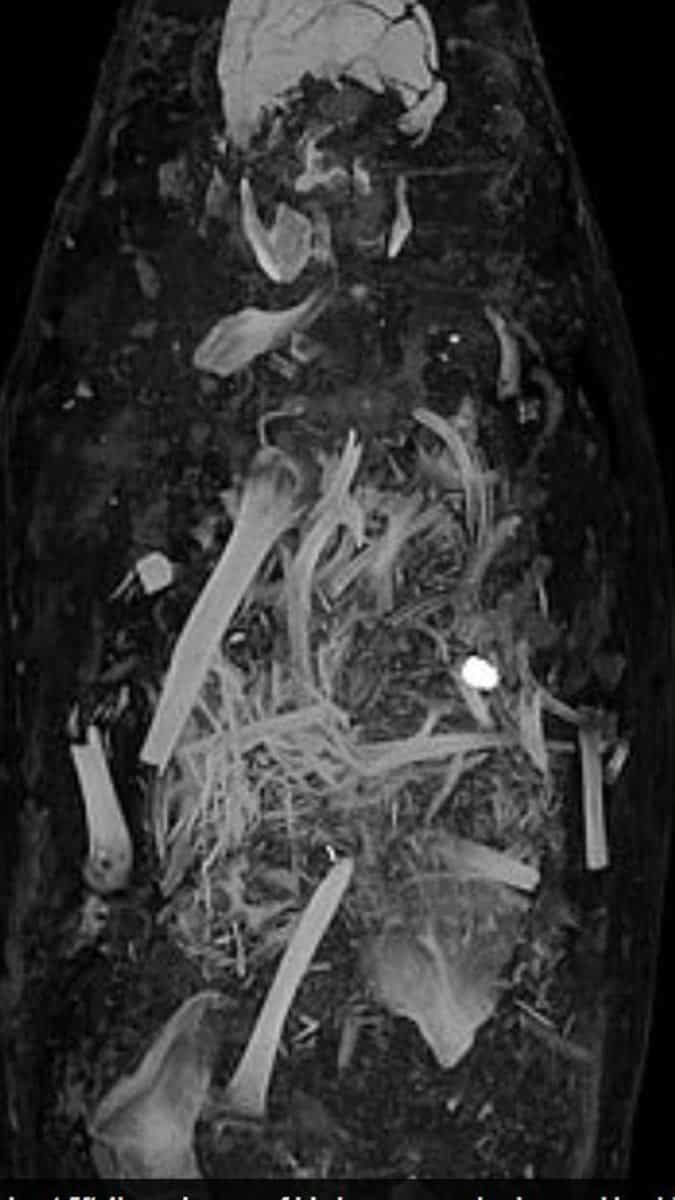

Mısır’da 1615 yılında gömülen üç mumyanın detayları bilgisayarlı tomografi sayesinde ortaya çıktı.Yirmili yaşlarda bir erkek, otuzlu yaşlarda bir kadın ve 17-19 yaşları arasında bir genç kıza ait olan mumyaların, alçı kaplı tabutların içerisinde muhafaza ediliyor.

Bilimadamlarının bilgisayarlı tomografi ile incelediği mumyaların tüm organlarıyla birlikte mücevher ve altın sikkelerle gömüldükleri ortaya çıktı.